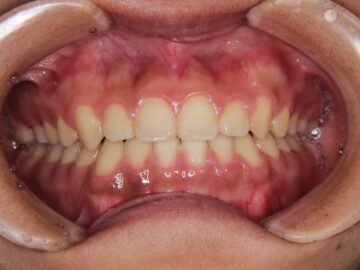

ご相談時

治療後

前歯にすき間がある。

上下顎全体にブラケットを装着し、隙間を閉じることを勧めた。